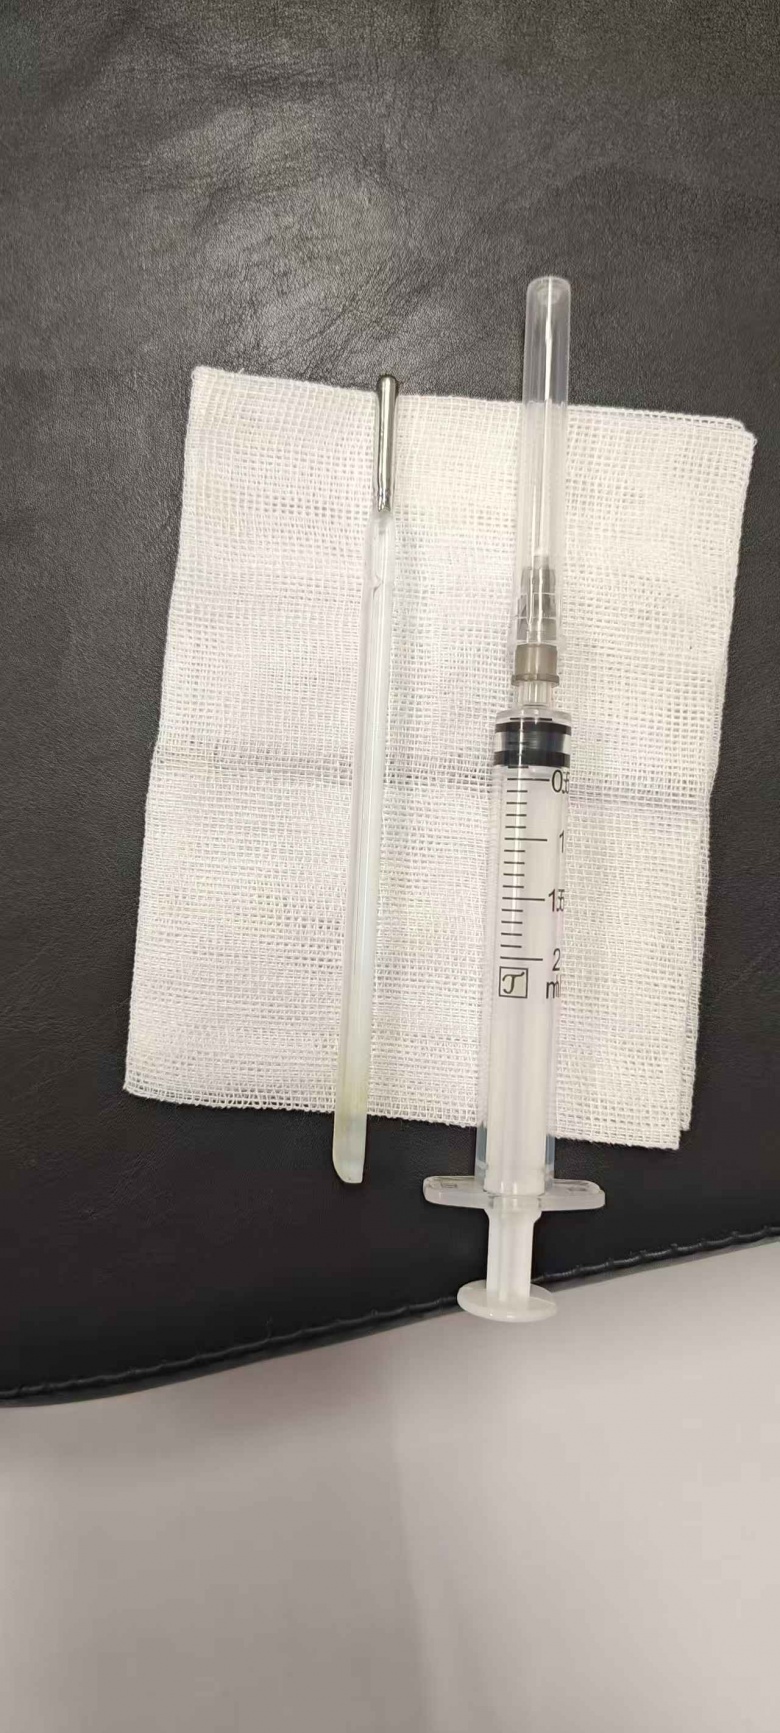

体温计滞留时间极长、位置较深,且毗邻关键的胆管和胰管,操作空间十分狭窄,稍有不慎就可能导致肠壁损伤。面对这一高风险病例,温州医科大学附属第一医院龙港院区的内镜中心医护团队在相应器械辅助下精准定位,用圈套器套住体温计一端,通过缓慢轻柔的提拉,成功将整根体温计从王先生的十二指肠处取出。

令人称奇的是

这根“跨越”了二十年的体温计

除刻度已消失外

外观基本完好无损